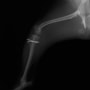

■ 症例22 ポメラニアン 1歳5か月 去勢雄

左後肢の挙上を主訴に来院した。整形学的検査、レントゲン検査より左右の膝蓋骨脱臼(左GradeⅡ〜Ⅲ、右Grade Ⅱ)を認めた。また、脛骨の前方引き出し試験の際に、引き出し兆候は認められないものの、疼痛が認められたため、前十字靭帯の損傷が疑われた。術中における、目視および関節内の操作によって、前十字靭帯の損傷や過伸展といった異常が認められなかったため、膝蓋骨脱臼の整復のみ実施した。手術手技は縫工筋及び内側広筋の解放、脛骨粗面の外側転位、滑車ブロック形造溝術、内外側関節包の縫縮を実施した。本症例は跛行もなく経過良好である。しかし、頸骨高平部の角度(TPA)が 右26.2°、左24.9°であり、解剖学的に前十字靭帯損傷のリスクが高いことから今後の経過に注意が必要である。